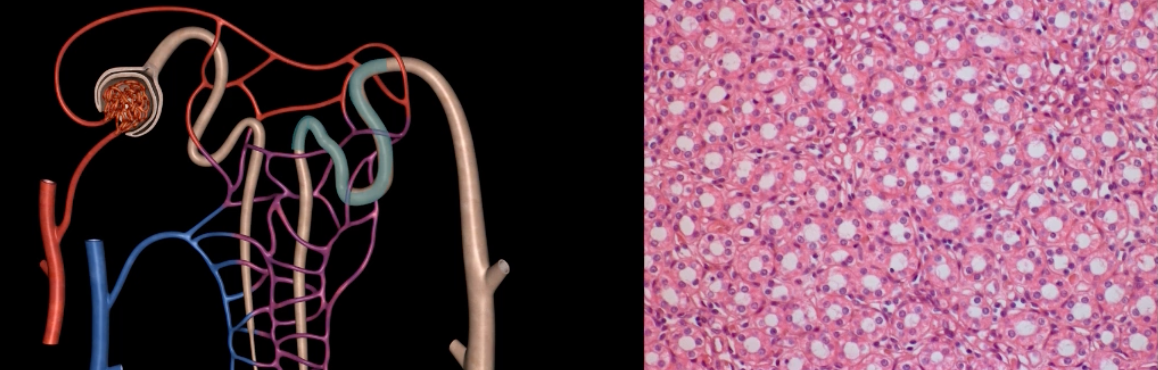

yellow: cortical nephron

blue: juxtamedullary nephron

yellow:

blue:

pink: podocyte

purple: pedicels

pink:

purple:

microvilli = purple

proximal convoluted tubule = green

right image: purple and green